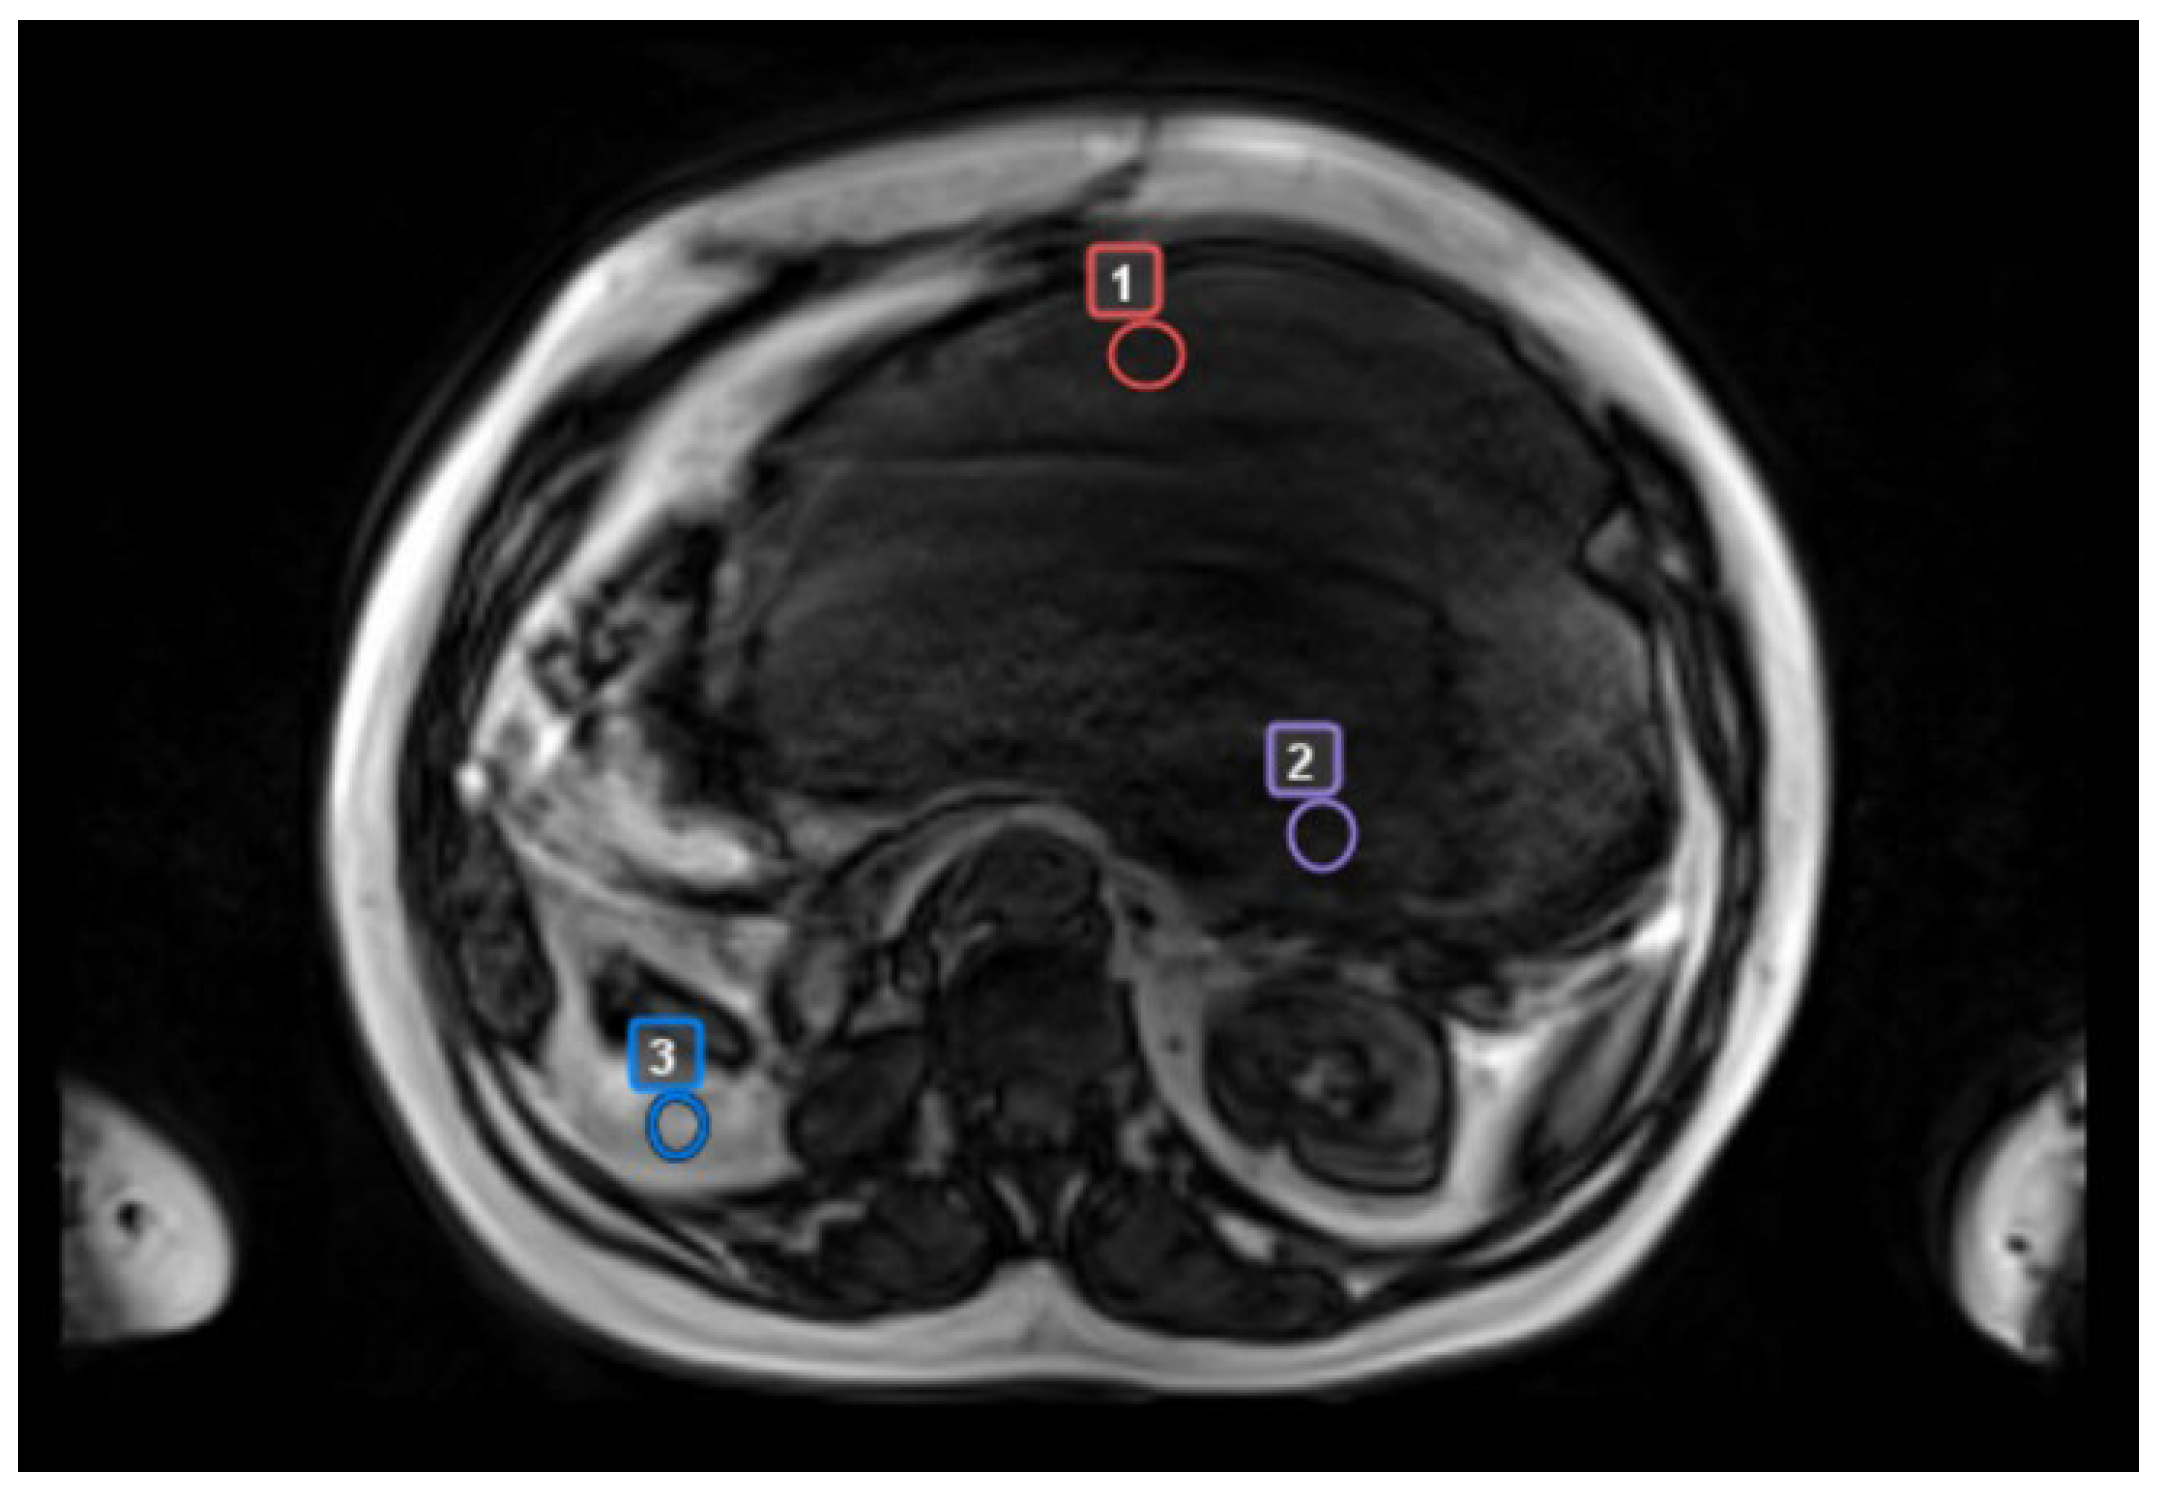

- biopsy site (precisely identified in patients who had CT scan-guided biopsies)

- “worst” tumor area with radiologic features suggestive of the most aggressive biology (reduction in ADC maps, high contrast enhancement, low T2 signal)

- “best” tumor area with the least aggressive radiologic features (lack of one or more aggressive features)

- a control area, identified as normal adipose tissue located in the same body region but separate from tumor tissue